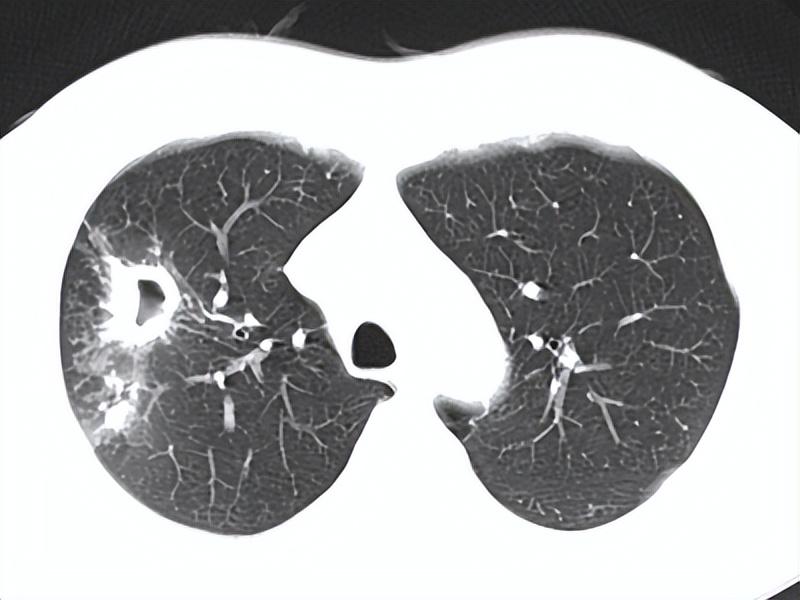

17岁的小徐是一名高三学生,即将面临高考。然而,寒假结束回校后,他却在肺结核筛查中呈阳性,进一步检查确诊为耐药肺结核。令人惊讶的是,小徐之前没有任何咳嗽、咳痰等典型症状,身体状况良好。这个案例引发了人们对耐药肺结核的关注和思考。

小徐的案例之所以特殊,是因为他属于无症状感染者。事实上,在肺结核患者中,约有40%是无症状感染者。此外,约20%的人口是结核潜伏感染者,这部分人群约5%-10%会在其一生中发展为活动性肺结核。这些数据表明,仅依靠症状来识别肺结核患者是远远不够的。